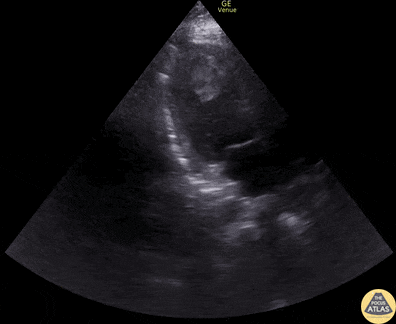

40s M with PMH HTN/HLD with no known CHF history presented with BLE edema, dyspnea, orthopnea, and weight gain. POCUS performed shortly after arrival showed markedly reduced LVEF with apical LV thrombus. The patient was initiated on a heparin drip and admitted, where formal TTE and right and left heart caths confirmed HFrEF due to ischemic cardiomyopathy and 3v CAD. Ultimately this patient improved with medical therapy but had an acute massive embolism event to b/l femoral arteries, b/l renal arteries, and SMA about 1 week into his hospitalization despite being on heparin drip while bridging to warfarin. He went to the operating room with vascular surgery and interventional cardiology for extensive thrombectomies as well as angiography but ultimately died after requiring resection of ischemic bowel and later suffering a large hemispheric embolic CVA. Dr. Kathleen Joseph, PGY-4, Denver Health Residency in Emergency Medicine Dr. Cailin Frank, Fellow, Denver Health Ultrasound Fellowship